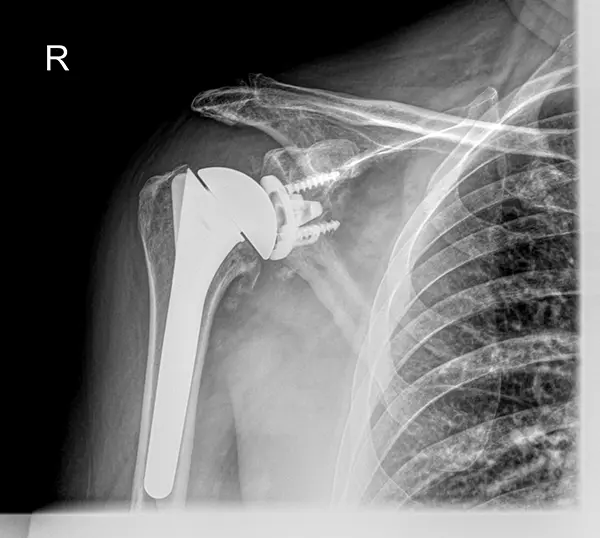

W przypadku braku znaczącej poprawy lub nasilania się objawów, warto rozważyć konsultację z chirurgiem. Przede wszystkim ma to na celu potwierdzenie, czy objawy są wynikiem choroby zwyrodnieniowej stawu barkowego. Po drugie, lekarz może ocenić, czy wskazane jest zastosowanie protezy stawu barkowego, jednocześnie wyjaśniając pacjentowi zasady, korzyści i ryzyko związane z taką procedurą.